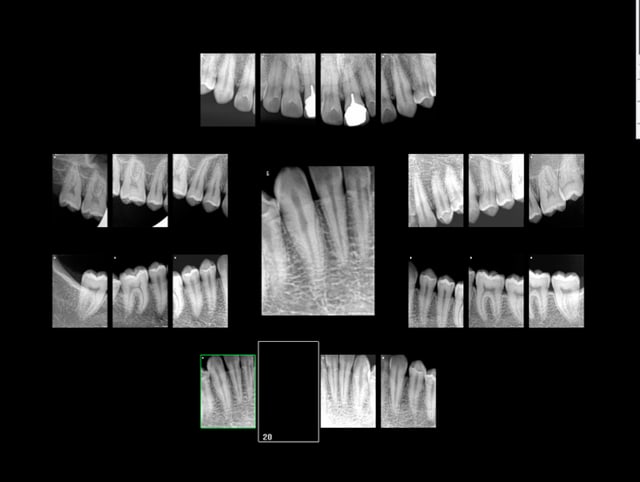

Dites moi dans votre consultation là. Mais il manque les radios recommandées par la HAS.

Examen incomplet : Indu. -)